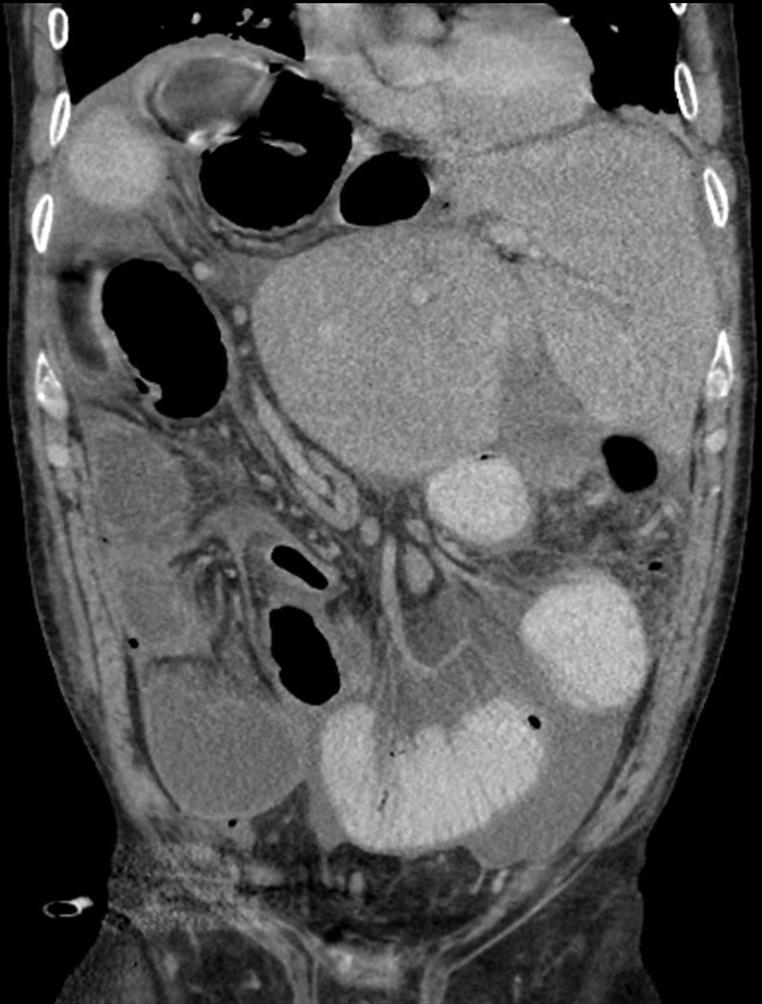

Een 56-jarige man heeft acute pijn links boven in de buik. Hij heeft vaker buikpijnaanvallen gehad. Op basis van CT wordt een langer bestaande torsie van het colon transversum vastgesteld, waarvoor patiënt wordt geopereerd. Op de CT-scan is ook een congenitale variant van de lever zichtbaar, met de rechter en linker leverkwab in twee aparte delen; de lever ligt rechts boven in de buik. Enkele maanden later wordt wegens vermoeden van een naadlekkage een nieuwe CT-scan gemaakt. Hierbij valt de lever opnieuw op.